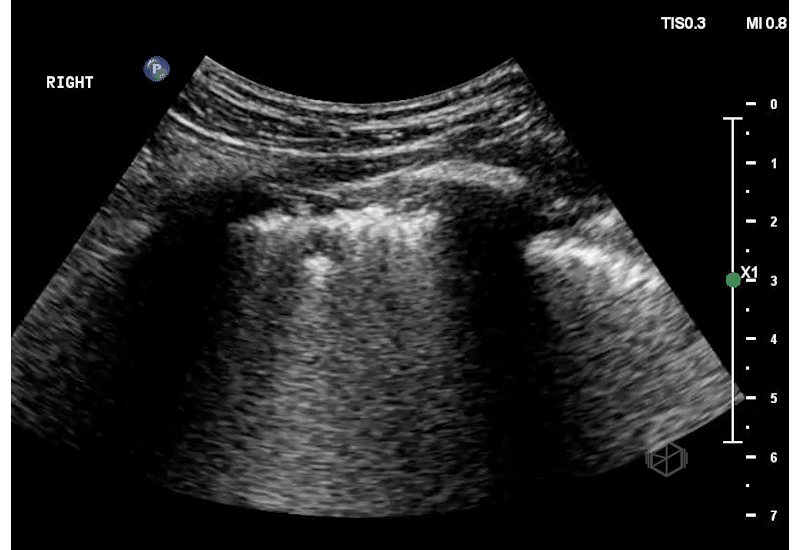

They had a 77-year-old male presenting to the ED complaining of shortness of breath. The patient had a history of CHF and multiple episodes of pneumonia. He was tachypneic, tachycardic, and hypoxic. The team did a POCUS of the lungs and saw the following.

This patient has B-lines, but note the irregular pleural borders that appear jagged. These are subpleural consolidations. In the correct clinical context, subpleural consolidations are a sign of infectious process although they can also be found in other pathologies as well.

Diagnosis: Multifocal pneumonia